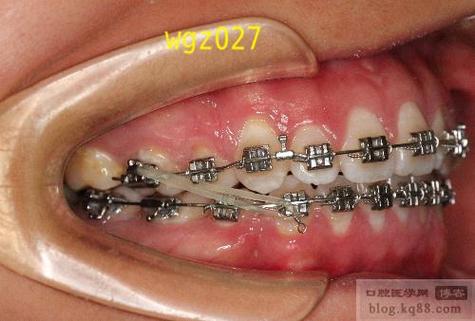

患者上颌中线偏斜3mm,需通过方丝滑动法关闭间隙,标记方丝中点后,以中点为基准,在偏移侧增加2mm的牵引钩,对侧不加,通过橡皮链牵引使两侧牙齿向中点对称移动,最终纠正中线。 -

asymmetric牙弓调整:

患者左侧牙弓长度较右侧短2mm,方丝中点标记后,左侧方丝末端需多剪2mm,避免弓丝末端过长刺激颊黏膜;同时通过弯制补偿曲,调整两侧牙齿位置,恢复牙弓对称性。